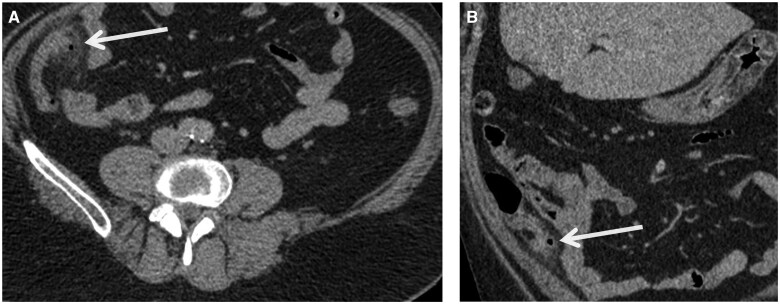

阑尾憩室炎,虽然罕见,是一个重要的鉴别诊断的情况下,右髂窝疼痛。以前,由于其临床表现相似,常被认为是急性阑尾炎的一种变体。然而,最近的研究表明,阑尾憩室炎是一个独特的临床实体,具有不同于急性阑尾炎的人口学特征和临床特征。它还与严重发病和死亡的高风险相关,需要及时诊断和管理。在此报告中,我们报告了一例58岁男性蚓状阑尾憩室炎患者,并回顾了相关文献。我们描述的分类阑尾憩室病和憩室炎,他们的临床表现,和他们的潜在并发症。我们概述了阑尾憩室炎和急性阑尾炎的影像学表现,并讨论了诊断成像在区分这两种疾病中的重要作用。

Appendiceal diverticulitis, although rare, is an important differential diagnosis in cases of right iliac fossa pain. Previously, it has often been considered as a variant of acute appendicitis, due to its seemingly similar clinical presentation. However, recent research indicates that appendiceal diverticulitis is a distinct clinical entity, with demographic characteristics and clinical features that are different to acute appendicitis. It is also associated with higher risk of severe morbidity and mortality, necessitating timely diagnosis and management. In this report, we present a case of a 58-year-old male patient with diverticulitis of the vermiform appendix and review the relevant literature. We describe the classification of appendiceal diverticulosis and diverticulitis, their clinical presentation, and their potential complications. We outline the radiological findings of appendiceal diverticulitis and acute appendicitis and discuss the important role of diagnostic imaging in distinguishing between these 2 conditions.